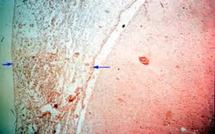

Santé: La méningite fait 02 morts à Fatick

| 16/04/2012

|

Société

L’épidémie de la méningite qui s’est incrustée au Sénégal ces derniers temps commence sérieusement à faire des ravages. Cette maladie d’inflammation des méninges à laquelle les enfants et les adultes restent les plus vulnérables a fait deux morts dans la région de Fatick, avec 45 cas enregistrés....